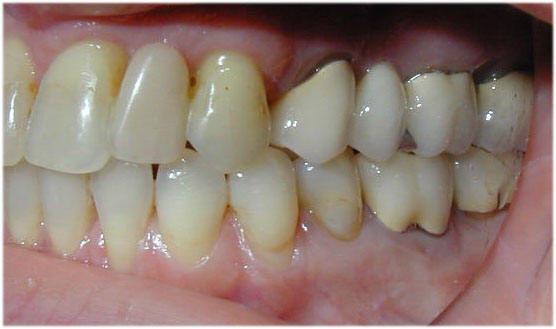

Fall-2

Bei einer jungen Frau waren die zweiten Schneidezähne im Oberkiefer nicht angelegt gewesen. Der linke Milchzahn war noch vorhanden aber nicht mehr erhaltungsfähig. Die mittleren Schneidezähne waren nach rechts gewandert. Die fehlenden Zähne sollten durch Implantate ersetzt werden. Dafür wurden die mittleren Schneidezähne in die Mitte zurückbewegt, um für Implantatversorgung Platz zu schaffen. Die Behandlung mit Invisalign hat 6 Monate gedauert.